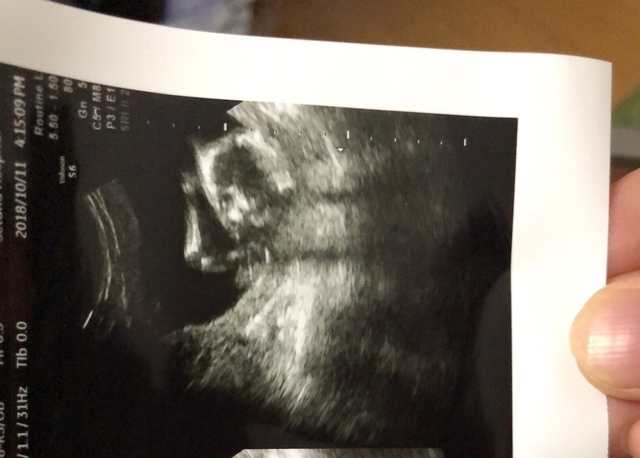

15週4日(15w4d・女の子)|ぱに0303 さん(28歳)

エコー写真撮影時のエピソード:

安定期を目前に突然始まったつわりに苦しんでいた頃のエコーです。お顔は隠していたけど、小さい手も足もかわいくて、お腹の中で大きくなっていることに夫婦でとても安心しました。

つわりで辛い度にこの写真を見て、いつか会える日を楽しみに頑張れました。エコー写真はお顔を隠したものばかりでしたが、4ヶ月の今はカメラを向けると絶対カメラ目線のカメラ大好きな娘になりました。